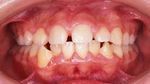

主な不正咬合の種類

このほかにも様々な不正咬合があります。

上顎前突150.jpg

→上顎前突 (出っ歯)

叢生150.jpg

→空隙歯列 (すきっ歯)→叢生

(でこぼこ、八重歯)